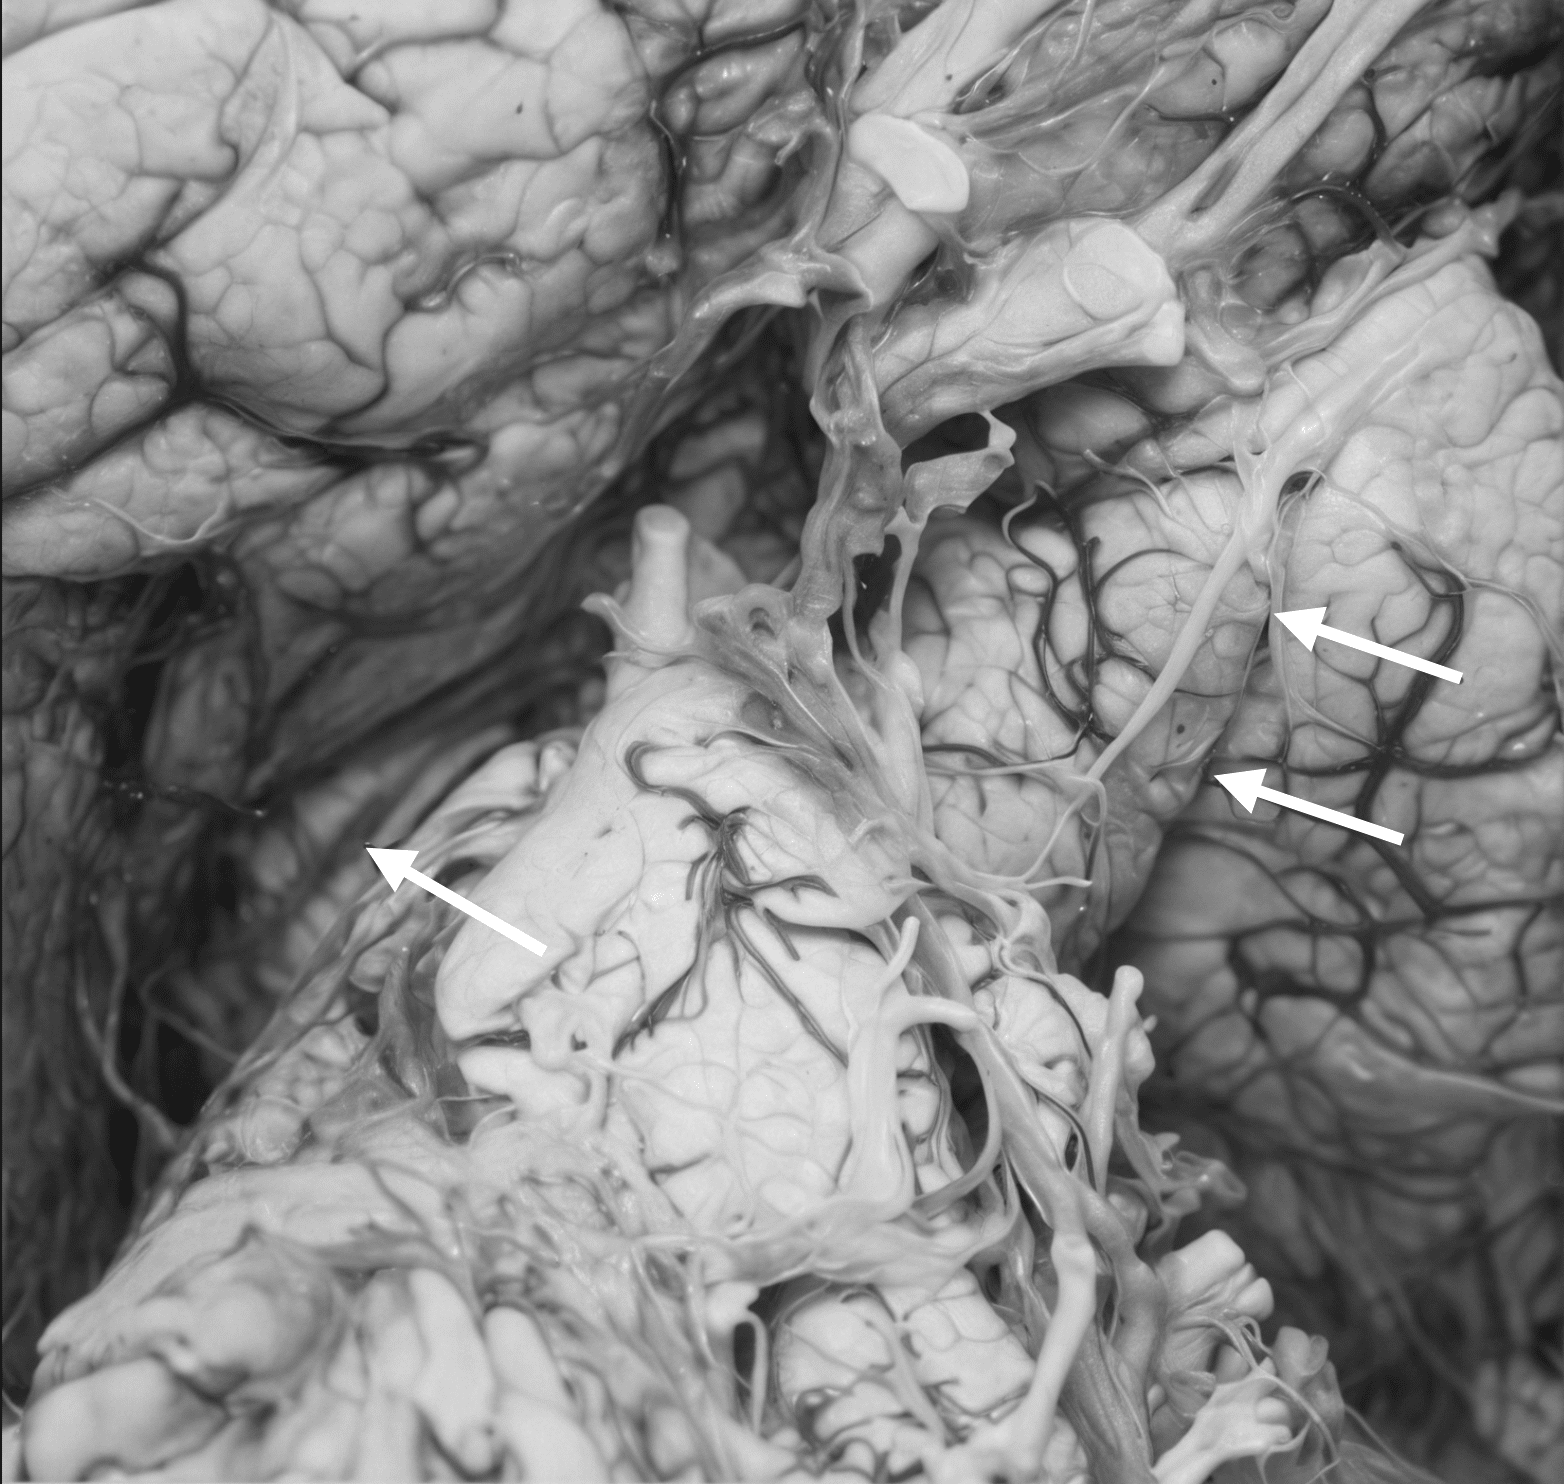

Although they didn’t coin the term “false localising sign” (which came later), the paper laid the conceptual groundwork by showing that pressure effects could mislead localisation. The paper also reproduced and expanded upon their 1928 figures, including gross anatomical images demonstrating the notch.

The notch itself was interpreted as a result of the contralateral cerebral peduncle being compressed against the rigid tentorial edge by midline brain shift. Over time, this mechanical force led to demyelination and necrosis of descending corticospinal fibres, the structural basis of the paradoxical hemiparesis.